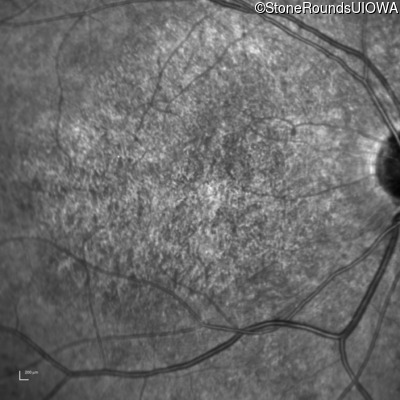

Infrared Fundus Photograph - Right - 10/125 -2 sc

Exemplar